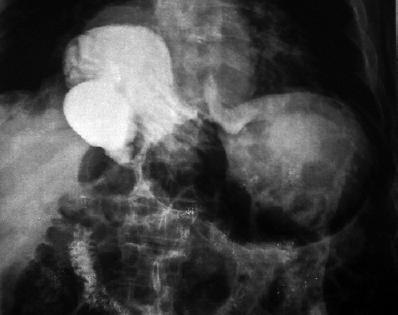

The patient was an 81 year old woman with arterial hypertension, and coronary disease in three arteries. She was bedridden due to a stroke which had occurred six months earlier. The patient was sent to our hospital for treatment of an intestinal obstruction. In the institution she had an upper digestive tract x-ray (Figure 1). When interviewed the patient described a 4 month long episode that had intensified in the previous 8 days. It was characterized by abdominal pain, vomiting, abdominal distension and melena. A physical examination showed generally poor physical condition, with dehydration, pain upon abdominal palpation, and left hemiparesis. The patient was referred for digestive endoscopy which found an organoaxial gastric volvulus and a hiatal hernia (Figure 2). Given the poor condition of the patient, and the absence of ischemia and gastric necrosis, it was decided to perform an endoscopic devolvulation using the technique described in 1995 by Tsang and colleagues (Figure 3).This technique has 6 steps. The initial aim is to create an alpha shaped loop (Figure 4) in the proximal end of the volvulated stomach. Next, the tip of the endoscope is advanced through the location of the stenosis produced by the volvulus. The following three steps aim to take the end of the endoscope to the duodenum (Figure 5). Once there, clockwise torque is endoscopically applied to complete the devolvulation (Figure 6). Since the patient was in poor condition, we decided to create two gastrostomies in the gastric wall: a distal gastrostomy for feeding, and one in the proximal body that was then sealed (Figure 7). The subsequent evolution of the patient was satisfactory.

Figure 2. UGI shows an organ-axial volvulus, note how the stomach has rotated on its vertical axis and the greater curvature is on the upper part of the screen while the lower curvature is in the lower part, contrary to what is normally found.